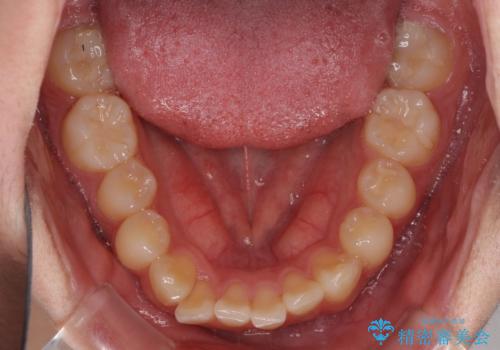

- 八重歯を気にして来院された高校生の患者様です。

ボディーコンタクトの激しい部活動を行っているため、補助装置とインビザラインを用いて、部活動を継続しながら治療を行うこととしました。

八重歯を効率よく改善するため、補助装置を使用して上顎の奥歯を後方に移動させました。

部活動をしながらでしたが、マウスピースをしっかりと装着してくださったので、1年半程度で終了することができました。